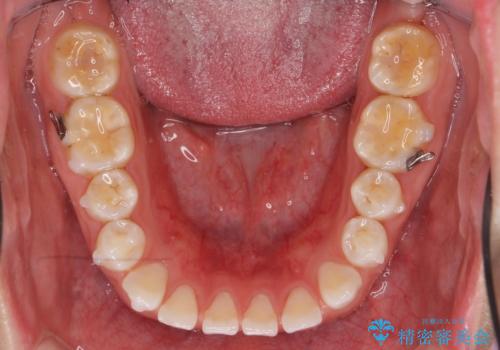

インビザライン 気になるすきっ歯の改善

- 上下顎前歯部の空隙が気になるので治したいと当院にいらっしゃった方の症例です。

非抜歯、インビザラインによる矯正治療により歯と歯の隙間および前歯の上下の隙間を閉じ切りました。